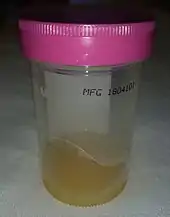

| Diagnostic method | Joint aspiration with culture[2] |

The synovial fluid should be collected before the administration of antibiotics and should be sent for gram stain, culture, leukocyte count with differential, and crystal studies.[11][13] This can include NAAT testing for N. gonorrhoeae if suspected in a sexually active person.[15]

Joint aspiration

In children, joint synovial fluid aspiration techniques aim at isolating the infectious organism by culture and sensitivity analysis. Cytological analysis of the joint aspirate can point to septic arthritis. However, a negative culture and sensitivity test does not rule out the presence of septic arthritis. Various clinical scenarios and technique-related factors may impact the validity of results of the culture and sensitivity. Additionally, results of cytological analysis, though important, should not be interpreted in isolation of the clinical settings.[5][25]

In the joint fluid, the typical white blood cell count in septic arthritis is over 50,000–100,000 cells per 10−6/l (50,000–100,000 cell/mm3);[26] where more than 90% are neutrophils is suggestive of septic arthritis.[2] For those with prosthetic joints, white cell count more than 1,100 per mm3 with neutrophil count greater than 64% is suggestive of septic arthritis.[2] However, septic synovial fluid can have white blood cell counts as low as a few thousand in the early stages. Therefore, differentiation of septic arthritis from other causes is not always possible based on cell counts alone.[13][26] Synovial fluid PCR analysis is useful in finding less common organisms such as Borrelia species. However, measuring protein and glucose levels in joint fluid is not useful for diagnosis.[2]

The Gram stain can rule in the diagnosis of septic arthritis, however, cannot exclude it.[13]

Synovial fluid cultures are positive in over 90% of nongonoccocal arthritis; however, it is possible for the culture to be negative if the person received antibiotics prior to the joint aspiration.[11][13] Cultures are usually negative in gonoccocal arthritis or if fastidious organisms are involved.[11][13]

If the culture is negative or if a gonococcal cause is suspected, NAAT testing of the synovial fluid should be done.[11]

Positive crystal studies do not rule out septic arthritis. Crystal-induced arthritis such as gout can occur at the same time as septic arthritis.[2]

A lactate level in the synovial fluid of greater than 10 mmol/L makes the diagnosis very likely.[27]